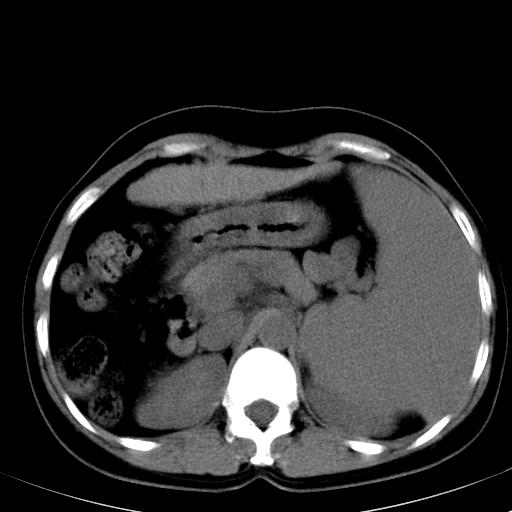

标题: CT19818:女40,脾大伴贫血,无肝炎病史 [打印本页]

标题: CT19818:女40,脾大伴贫血,无肝炎病史

血常规血红蛋白102,

骨穿,诊断再障,无其他病史

脾大符合临床诊断(再障)。

巨脾。

肝硬化、门脉高压、脾大。再障+肝硬化促成巨脾。